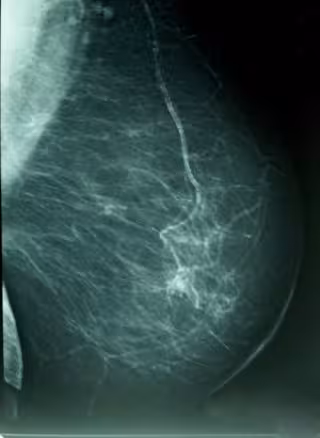

En la mujer, el tumor maligno de mama es el más frecuente como causa de muerte, con 229 fallecimientos --cuatro por ciento del total de muertes y 17 por ciento del total de tumores-- presentando tasas superiores a la media nacional en 2009.

También es la primera causa específica de Años Potenciales de Vida Perdidos --11 por ciento--. Desde 2000, la mortalidad por esta causa presenta una disminución del 10 por ciento.